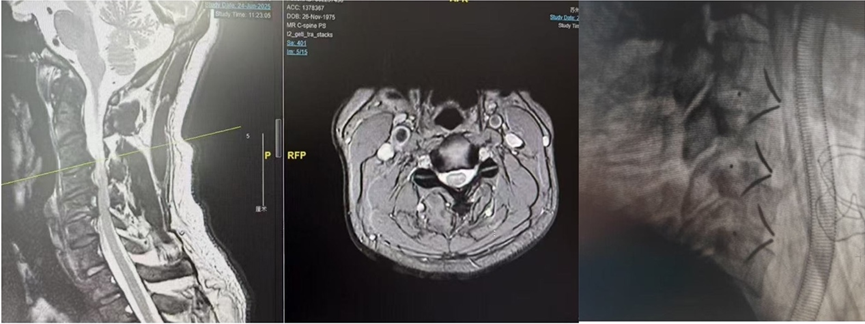

技术护航,挑战「不可能」: 凭借术中神经监护等先进技术,团队成功驾驭多例高难度急诊手术,如合并血管损伤的复杂骨盆骨折复位固定、颈椎外伤伴脊髓损伤的紧急减压融合术,以精湛技艺守护救治的安全与精准。

脊柱外科,突破「手术禁区」: 面对寰枢椎脱位、重度腰椎间盘突出等高难度挑战,团队创新应用侧块固定融合技术、UBE(单侧双通道内镜)、OSE(单侧双通道脊柱内镜)等微创利器,高效解除患者病痛。术后患者恢复迅速,常能在 2-3 天内下床活动。